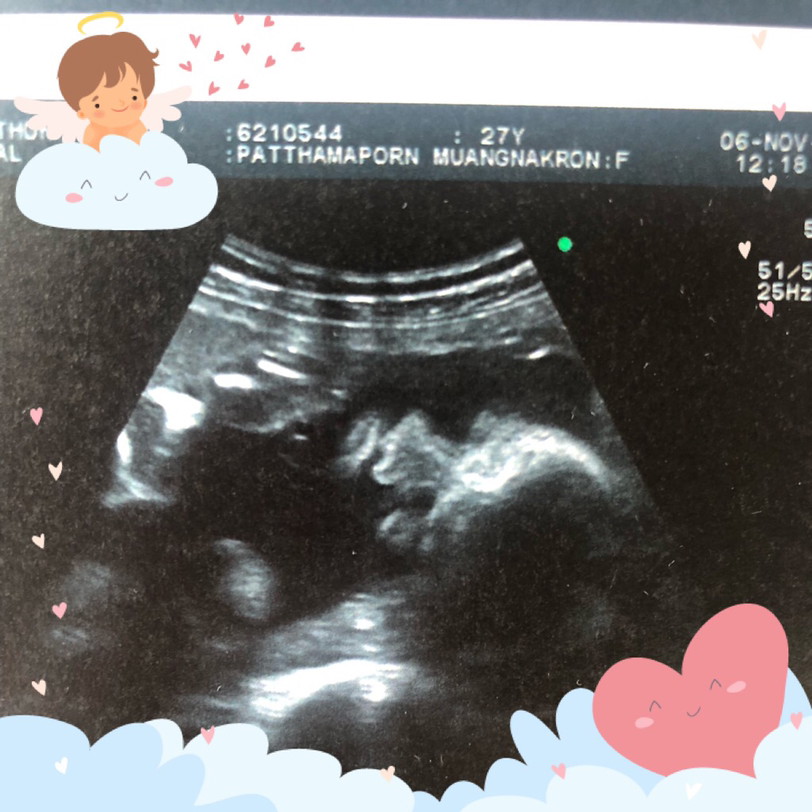

แม่ๆบ้านใหนคลอดเดือนมีนาคมเมษายนบ้างค่ะ ขอดูภาพอัตตราซาวหน่อยจ้าว่าโตแค่ใหนแล้ว